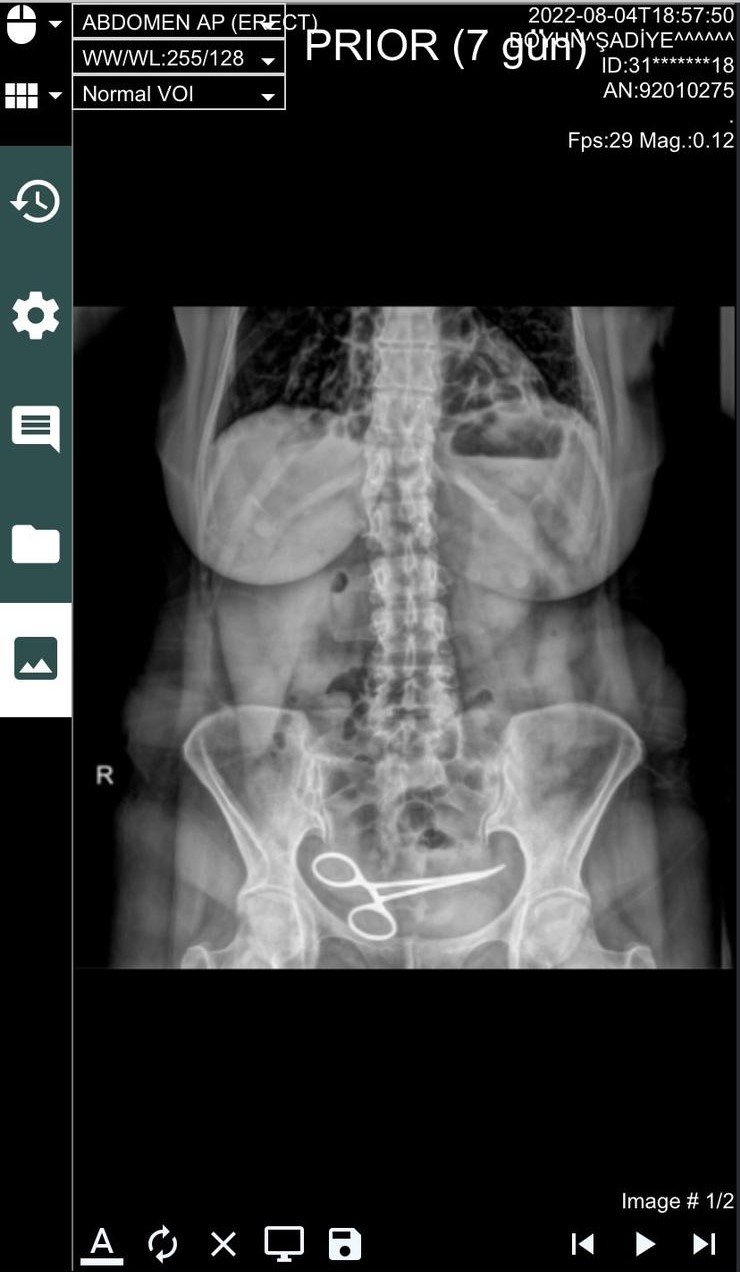

Ankara'da Şadiye Boyun, 28 Aralık 2021 tarihinde Pursaklar ilçesinde, özel hastanede bir kadın hastalığı nedeni ile ameliyat oldu. Ameliyattan 8 ay sonra karın ağrısı şikayeti görülen Boyun, ambulans ile Pursaklar Devlet Hastanesi'ne kaldırıldı. Burada çekilen röntgende Boyun'un ince bağırsağına takılı 12 santim boyunda makas olduğu görüldü. Ardından iddiaya göre, ameliyatın gerçekleştirdiği özel hastaneye haber verildi. Özel hastaneden görevliler geldi. Görevliler tarafından tekrar özel hastaneye götürülen Boyun'un röntgeni çekildi. Bunun üzerine oğlu Fatih Boyun, durumdan şüphelenerek e-Nabız uygulamasından röntgen sonuçlarına baktı ve annesini Gülhane Eğitim ve Araştırma Hastanesi'ne sevk ettirdi. Şadiye Boyun'un karnındaki makas ameliyatla alındı. Boyun, avukatı aracığıyla, ameliyatı gerçekleştiren doktor ve hastane hakkında suç duyurusunda bulundu.

Şadiye Boyun, yapılan hata nedeniyle büyük mağduriyet yaşadığını söyledi. Ameliyat olduktan yaklaşık bir ay sonra doktorların kontrol amaçlı kendisine gün verdiğini söyleyen Boyun, iyileşmeyi beklerken rahatsızlandığını belirterek, "Geçen yılı 5 Ağustos'ta sancılandım, ambulansı aradım. Ambulans beni Pursaklar Devlet Hastanesi'ne götürdü. Benden direkt röntgen istediler. Bana oradaki röntgeni çeken görevli, "Teyze senin cebinde makas mı var?" diye sordu. Ben de "Oğlum ne makası, bende makas filan yok" dedim. Üzerimi kontrol etti ve "Sende makas var" dedi. Beni direkt gözetim odasına götürdüler. Benden röntgeni isteyen doktor da oraya geldi ancak bana makas olduğunu söylemedi. Bana ameliyat olduğum hastaneyi ve doktorun adını sordu. Sonra bana gelip, "Seni almaya gelecekler diğer hastaneden, gider misin?" diye sordu. Ben de o olayın şoku ile gittim" dedi.

Özel hastanede tekrar muayene edildiğini söyleyen Şadiye Boyun, "Ben de, "Neyim var" diye sorudum. Bana ameliyat yerimin ödem ve apse yaptığını söylediler. Ben de içimde ödem değil makas olduğunu söyledim. "Niye makası saklıyorsunuz" diye sordum. Beni hemen odaya götürdüler. Sonra oğlum müdahale etti. Oğlum da yalan söylediklerini anlayınca benim röntgen sonuçlarımı istemiş. Sonuçları ona da vermemişler. Sonra oğlum da ambulans çağırdı. Gülhane Eğitim ve Araştırma Hastanesi'ne gittim. Orada o gece ameliyata alındım. Ameliyat güzel geçti ama 3 gün sonra tekrar sorunlar başladı. Ben kalp hastası olduğum için verilen narkozlar bende yan etki yapmış. Bir hafta sonra ben tekrar ameliyat oldum. 8 ay içinde 3 kere, 25 gün içinde ise 2 kere ameliyat oldum. Sorunlarım bitmiş değil, yine doktora gidiyorum. Ama bana bir kere özel hastane tarafından dönüş yapıp, "Geçmiş olsun, biz bu hatayı yaptık. Özür dileriz" bile demediler. Bana yapılan başkasına yapılmasın. Ben bu işi sonuna kadar götüreceğim" ifadelerini kullandı.

Fatih Boyun ise "Pursaklar Devlet Hastanesi'ndeki doktor, anneme açıklama yapmamakla beraber diğer hastanenin doktorunu arayıp, "ilgilenin" demiş. Onlar da özel araç yollayarak kendi hastanelerine götürmüşler. Kendi hastanelerinde annemi röntgen çekmek için aşağı indirdikleri sırada ben geldim. Başhekim de oradaydı. Ben başhekime, "Hocam durum nedir? diye sordum. Başhekim ameliyattan dolayı bir kan birikmesi olduğunu söyledi ve "Biz bunu boşaltacağız" dedi. Ben bu durumdan şüphelendim ve röntgen sonucunu görmek istedim. Beni sekreterliğe gönderdi, sekreterlik ise 12 saate kadar röntgen sonucunun çıkacağını söyledi. Ben de e- Nabız'dan Pursaklar Devlet Hastanesi'nde çekilen röntgen sonucuna baktım ve o arada makası gördüm. Ben orada konuşurken annemi odaya çıkardılar, ameliyata hazırlıyorlardı. Durumu fark edince ben doktorları çıkardım odadan ve annemin üzerini giydirip hastaneden uzaklaştım. Ben sosyal medyadan ameliyatı yapan doktora ulaştım. Röntgen sonucunu gönderdim ve "8 ay önce yaptığınız ameliyat" dedim ve başka hiçbir şey yazmadım. Doktor, "Üzgünüm, olmuş böyle bir şey" dedi. Sonradan doktor biraz kendini haklı çıkarmaya çalıştı. "Biz sadece ameliyatı yaparız, sayımı hemşireler yapar" dedi. Ama sonuçta yapılmamış bir şey var ortalıkta, malzemeler sayılmamış. Doktor imza atmış. Bu benim problemim değil. Şu an davamızı açtık, dava gününü bekliyoruz. Adalete güveniyoruz" diye konuştu.